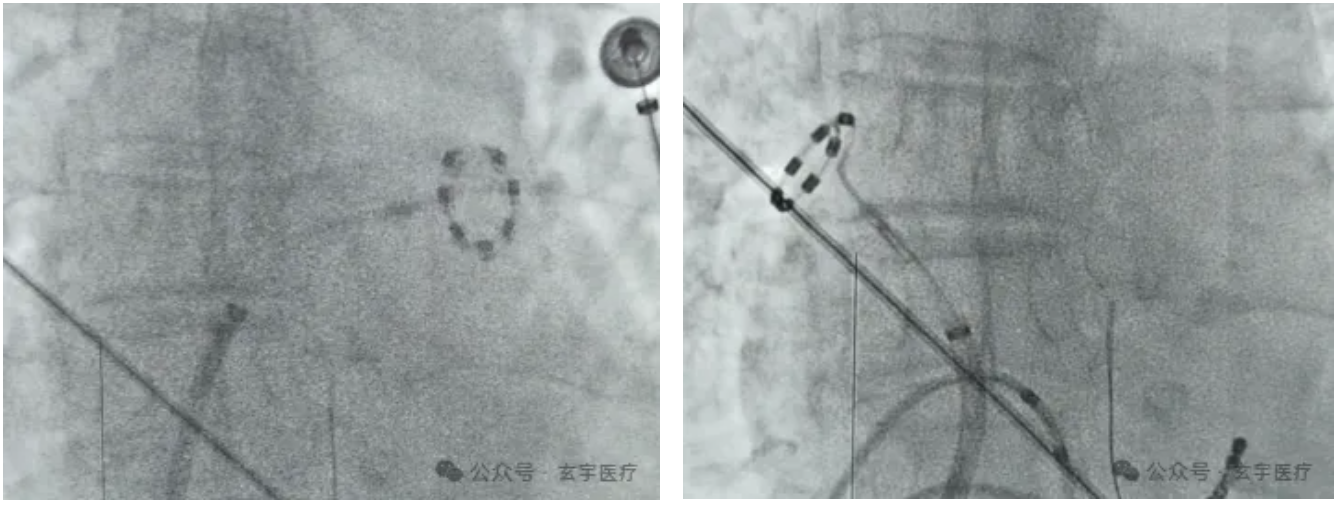

建模完成后将RhythPulse® PFA导管送至右上肺静脉,电压图提示患者左房基质良好。随后从右上肺静脉开始,进行双侧肺静脉隔离。其中右侧肺静脉放电23组,左侧肺静脉放电27组。脉冲放电结束后进行了起搏验证,实现了肺静脉电位双向阻滞,术后电压图均提示双侧肺静脉均隔离完成。整体消融过程耗时约40分钟。

两侧肺静脉隔离过程